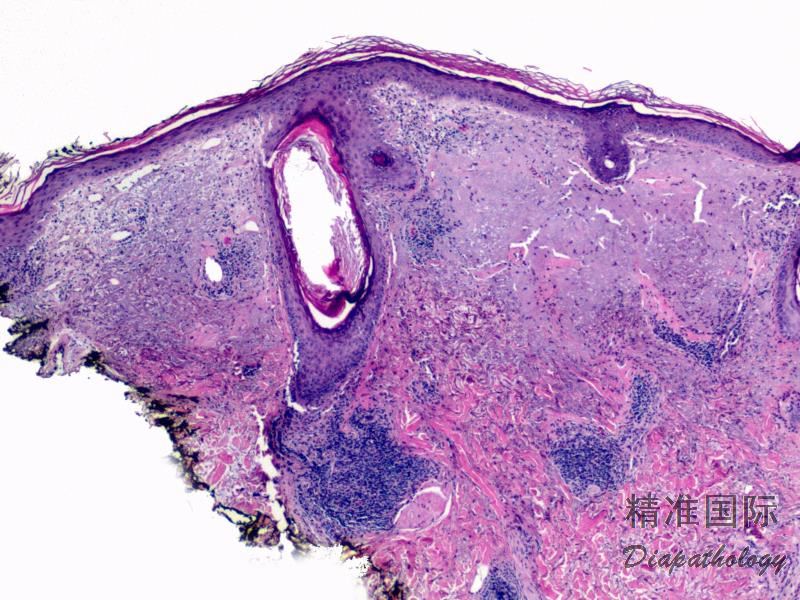

镜检:表皮角化过度,毛囊扩张和角质栓,棘层萎缩。表皮及毛囊上皮基底细胞液化变性,可见坏死角质形成细胞。真皮浅层水肿,毛细血管扩张,血管及附属器周围大量淋巴细胞浸润,可见浆细胞浸润。晚期损害可见基底膜增厚。可有糜烂和溃疡。